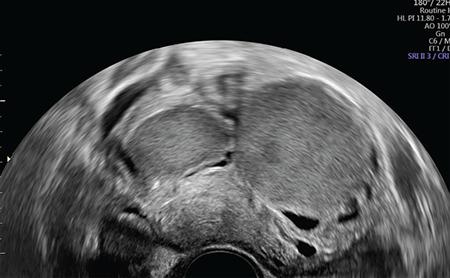

子宫内膜异位症治疗中的围手术期注意事项。

Perioperative considerations in the treatment of endometriosis.

Endometriosis is one of the most common benign diseases in women of reproductive age. Nearly all gynecological offices and clinics will contain patients with endometriosis; the frequency and severity of the disease will vary from one setting to another. Adjoining specialties, such as internal medicine, general medicine, surgery, urology, orthopedics, neurology and psychosomatic medicine, will be challenged directly or indirectly by various forms of endometriosis and its sequelae. The disease is characterized by pelvic pain, dysmenorrhea, dyspareunia and sterility. Even now, several years may elapse between the onset of the disease and its diagnosis. The diagnosis of endometriosis is complicated by the diversity of the symptoms. A precise documentation of the patient’s medical history and thorough diagnostic procedures are essential to establish a robust diagnosis. This article will discuss the perioperative considerations, diagnosis and treatment of endometriosis.

摘要

子宫内膜异位症是育龄女性最常见的良性疾病之一。几乎所有妇科科室和诊所都会有子宫内膜异位症患者;该病的发病率和严重程度因地区而异。内科、普通科、外科、泌尿外科、骨科、神经科和心身医学等相关专科将直接或间接面临各种形式的子宫内膜异位症及其后遗症的挑战。该病的特点是盆腔疼痛、痛经、性交困难和不孕。即使到现在,从疾病发作到诊断仍可能会间隔数年。子宫内膜异位症的症状多样,这使得诊断变得复杂。准确记录患者的病史并进行全面的诊断程序对于做出可靠的诊断至关重要。本文将讨论子宫内膜异位症的围手术期注意事项、诊断和治疗。